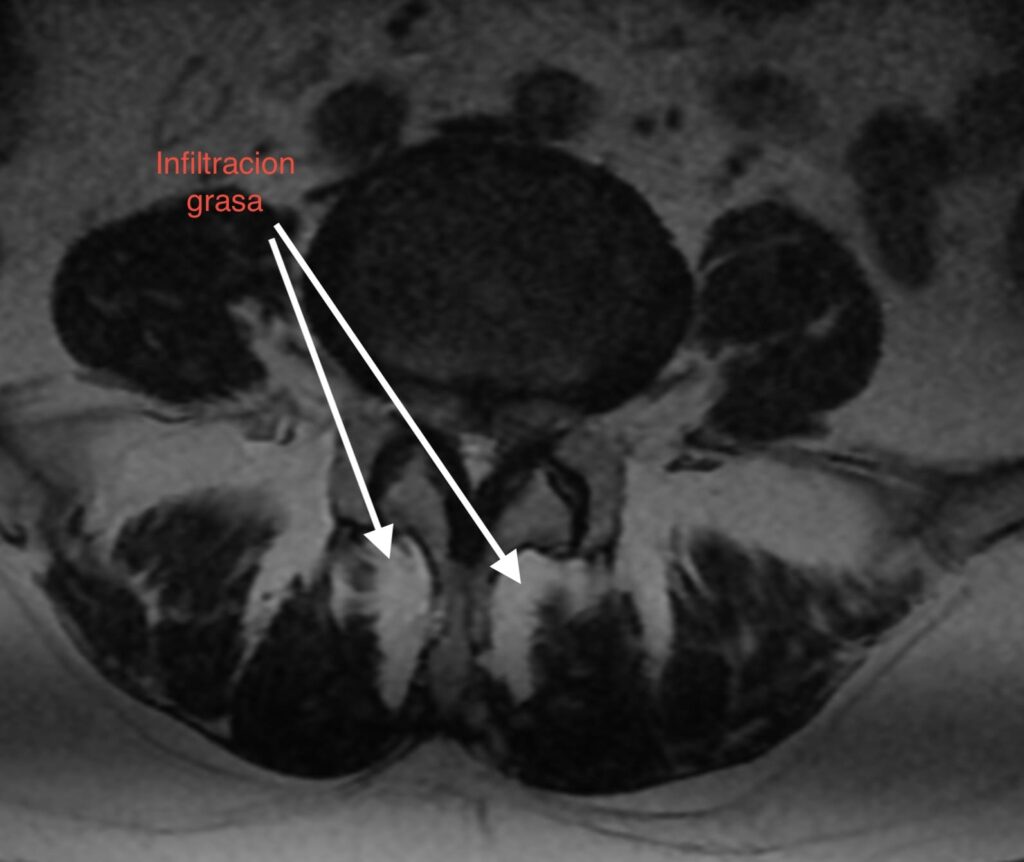

1. Pérdida del «Tirante» Dinámico: Los músculos multífidos actúan como estabilizadores segmentarios finos. En pacientes sarcopénicos, estos músculos son reemplazados por tejido adiposo no contráctil, perdiendo su capacidad de tensión.

• Calidad vs. Cantidad: La infiltración grasa (clasificación de Goutallier o medición de unidades Hounsfield en TAC) en el multífido es un factor de riesgo independiente para la reintervención. Músculos con alta infiltración grasa se correlacionan con peores resultados funcionales (ODI) y mayor tasa de complicaciones mecánicas como la cifosis de la unión proximal (PJK).

1. Screening Preoperatorio Rutinario: La RM lumbar debe utilizarse para evaluar la calidad muscular (corte axial en L3/L4), no solo la patología neural.

La sarcopenia y la infiltración grasa paravertebral no son hallazgos incidentales del envejecimiento, sino determinantes activos en la vida útil de una artrodesis lumbar. La atrofia muscular deja al disco adyacente desprotegido frente al estrés mecánico incrementado post-fusión. Identificar y tratar la sarcopenia es imperativo para reducir la incidencia de reintervenciones y mejorar la calidad de vida a largo plazo del paciente.